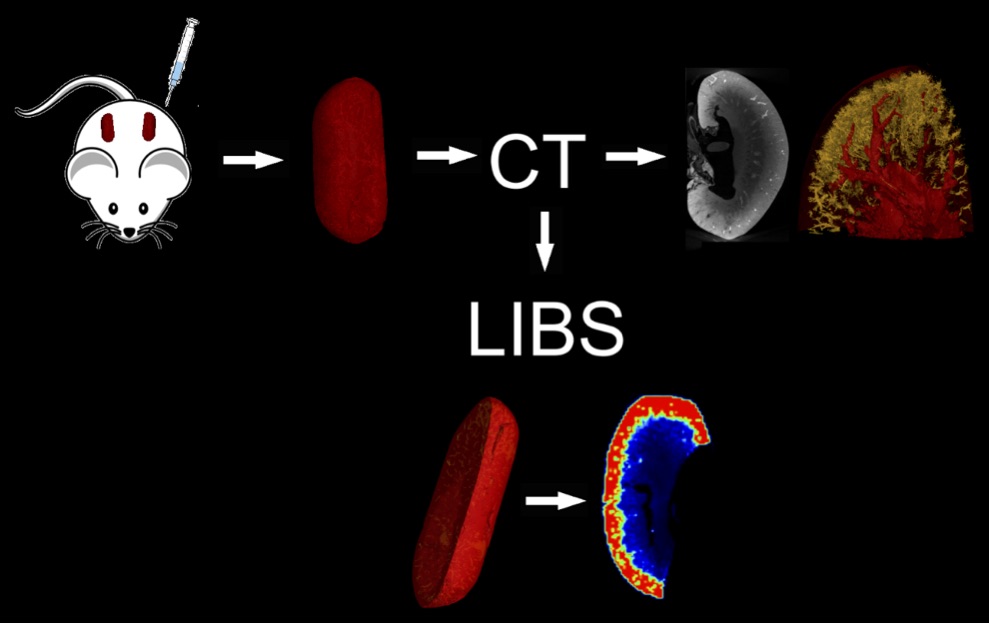

X-Trace LIBS Telemetry Element Analysis System - LIBS in-situ elemental analysis mobile laboratory LIBS technology comprehensive application solution: including MicroLIBS, μCT and LIBS 3D imaging system technology solutions (AtomTrace research team first combined application of μCT and LIBS technology in the world) , see the following application case scheme), biological application program, ecological and environmental science application program, soil science application program, geological minerals (including jewelry identification) application program, material science application program, archaeological and cultural relic identification application program, criminal investigation Application programs, medicines, including Chinese medicine research application programs and other project cooperation: including sample test analysis, sample chemistry two-dimensional or even three-dimensional distribution construction, professional field application cooperation and paper publishing, talent joint training (such as doctorate, etc.) and LIBS technical training AtomTrace, such as laboratory cooperation, provides you with the world's most comprehensive and comprehensive LIBS analysis technology solution!

ü Can be combined with μCT for 3D imaging analysis for medical diagnosis, etc.

The CEITEC/Atomtrace LIBS research team not only used LIBS technology to make complete leaf element distribution maps, but also used LIBS technology to combine with micro-CT (μCT) for 3D chemical imaging construction. The above research results have established the leading position of LIBS technology in the laser spectroscopy laboratory represented by Dr. Kaiser and others in the field of global life and environmental science applications.

The left picture shows the micro-CT of the root section of the sunflower, and the right picture shows the distribution of the lead metal in the sunflower root (from J. Kaiser et al., 2007).

In 2010, the laser spectroscopy laboratory represented by Kaiser used LIBS technology combined with μCT technology to study and analyze the distribution of spine bone elements including Ca, Al, P, Na, etc. of snake deformity osteitis, and published "Investigation of The osteitisdeformans phases in snake vertebrae by double-pulse laser-induced breakdown spectroscopy" (Anal. Bioanal. Chem. 398:1095-1107, 2010)

The CEITEC/Atomtrace Laser Spectroscopy Laboratory has conducted extensive research on the application of LIBS in geology and mineral resources. In 2014, "Two dimensional elemental mapping by laser-induced breakdown spectroscopy" (Spectroscopy Europe 26 No. 6: 6-10, In the 2014 academic paper, the surface element distribution of arsenic platinum ore, chalcopyrite Pt, Pb, Ni, etc. was constructed in 2D and even combined with μCT.